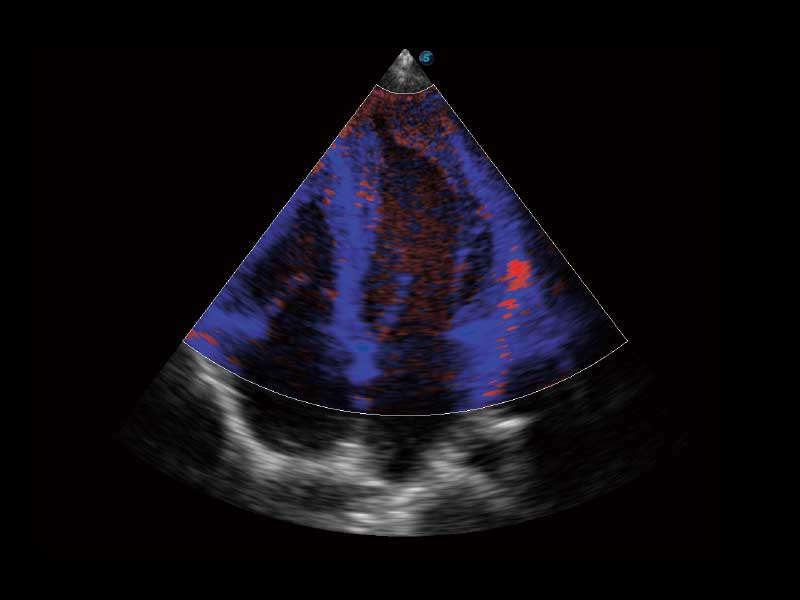

E2便携式彩色多普勒超声诊断系统采用专业的超声技术平台、高度集成化的硬件模块和结构设计、简便的操作流程、多探头接口设计,兼顾了优质图像、轻便机身以及台便两用的临床使用需求。

μ-Scan微米成像、空间复合成像、高分辨率血流成像。